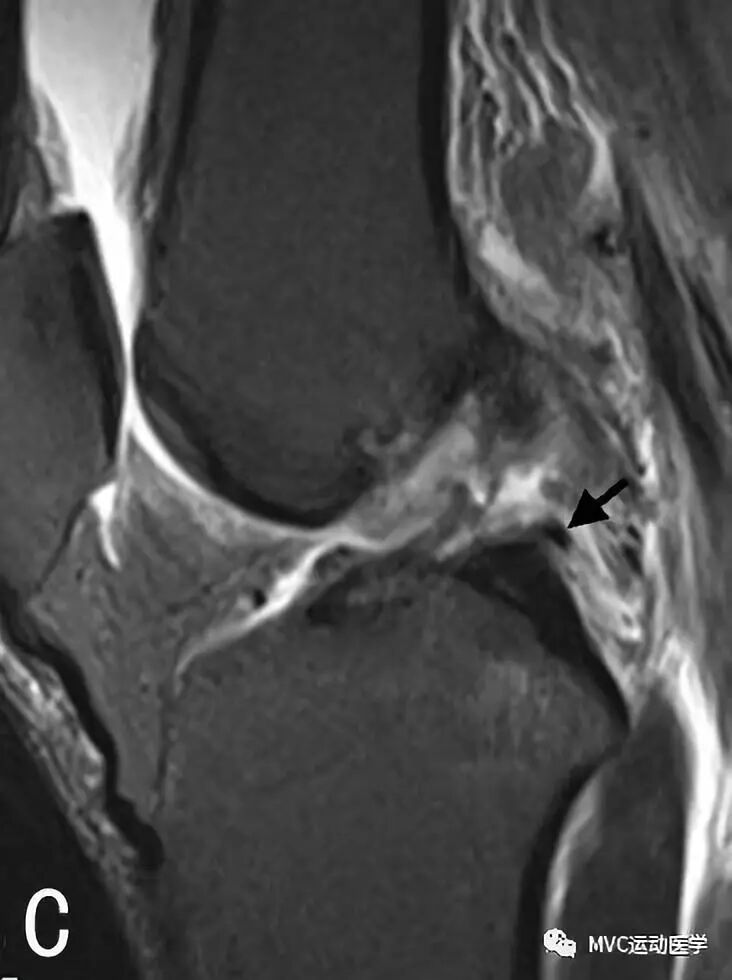

B:矢状位MRI连续扫描,黑色箭头所指为Wrisberg韧带

C:矢状位MRI连续扫描,黑色箭头所指为Wrisberg韧带

D:矢状位MRI连续扫描,黑色箭头所指为Wrisberg韧带,白色箭头所指为Humphrey韧带;